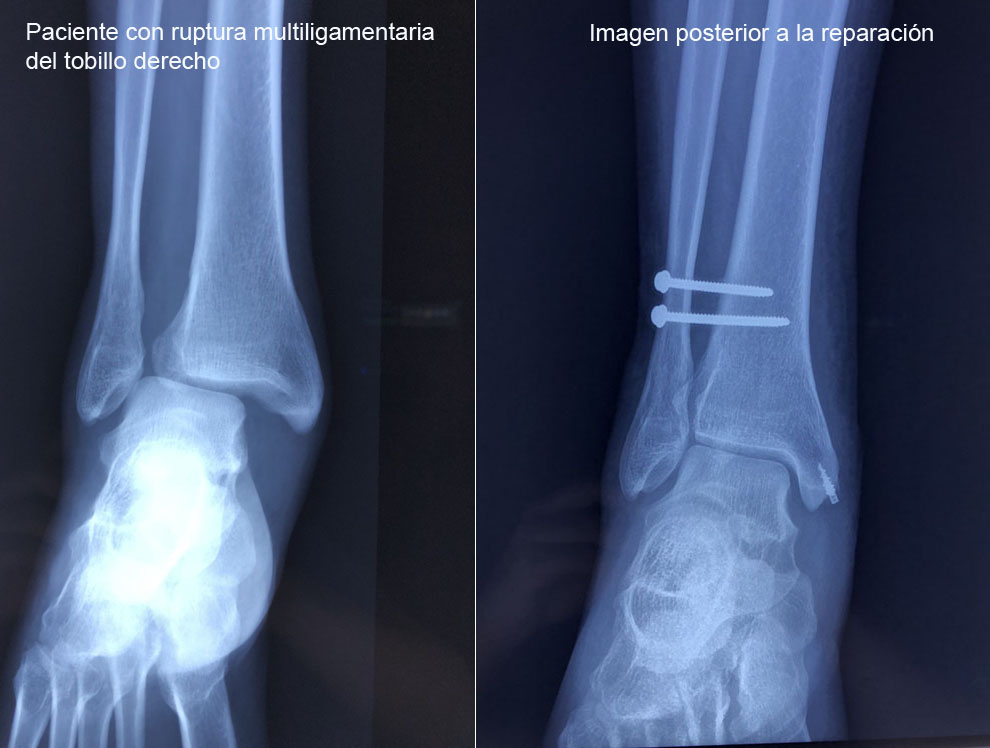

Los esguinces son lesiones ligamentarias que pueden variar en diversos grados de severidad, los cuales pueden ser desde una simple distensión de las fibras hasta una rotura total de las mismas. Por lo que es indispensable una adecuada valoración y un tratamiento oportuno para evitar las complicaciones.

Ruptura del Ligamento Peroneo Astragalino Anterior

Es el ligamento que con mayor frecuencia se lesiona cuando presentamos la inversión forzada del tobillo, este se encuentra en el borde anterior del maléalo lateral hasta la región adyacente del astrágalo.

Ruptura del Ligamento Deltoideo

El ligamento deltoideo es el principal estabilizador medial del tobillo, evita que el tobillo se vaya en eversión. El ligamento está formado por dos capas. Su ruptura condiciona inestabilidad medial del tobillo.